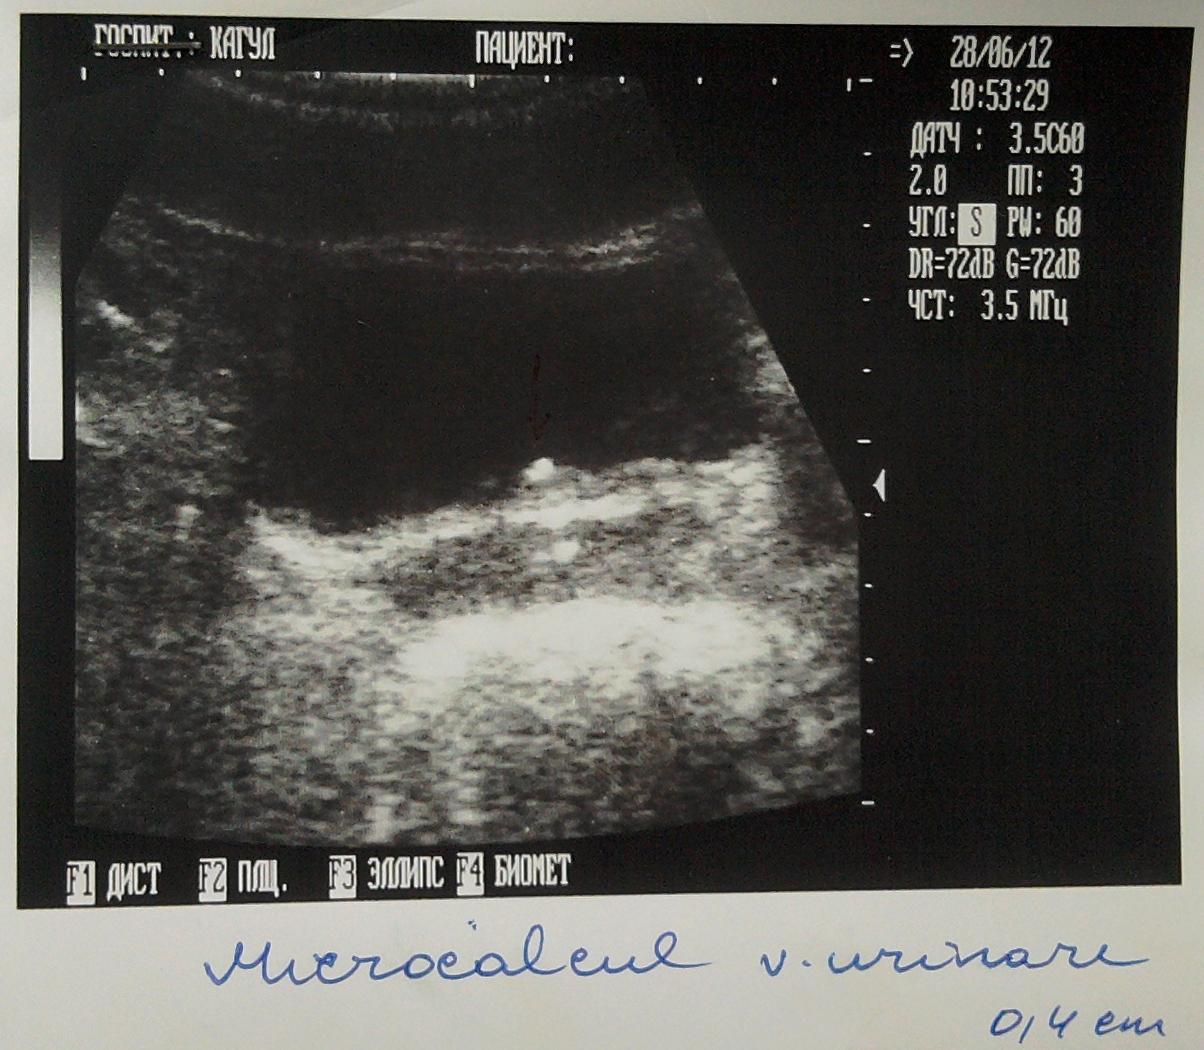

Здравствуйте я зделал год назад узи мочевого пузыря и у меня обнаружили камушек размером в 0,4 см, потом я посетил местного уролога он назначил мне Шилинтонг по 3 таблетки 3 раза в день. Я иногда по 4 пил.

- Через пол года я опять зделал узи и камушек как стоял так и стоит, после этого я пошол к врачу он решил что они видят не камушик а что-то с простатой и взял анализ( анализ нормальный как он мне сказал ) и сказал что это наверное кальцинат и не надо не какого личения. Чтоб я опять через пол года зделал узи.

Ниже я прикрепил фото узи.

Такого размера кальцинат должен отойти незамеченным из мочевого пузыря. Сделайте МСКТ почек, мочеточников , мочевого пузыря и простаты.